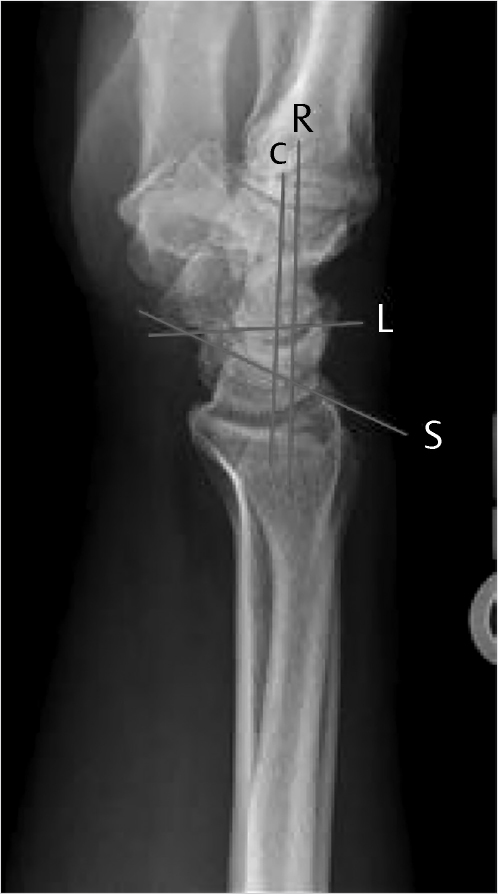

The hand and wrist has a total of 27 bones. The wrist is made of the distal ends of the radius and ulna, the eight carpal bones, and the proximal ends of the five metacarpals. The carpal bones consist of two rows of four bones each. The proximal row includes radial to ulnar, the scaphoid, lunate, triquetrum, and pisiform (Fig. 2‑1). The distal row includes radial to ulnar, trapezium, trapezoid, capitate, and hamate. The proximal carpal row is considered intercalated because no tendons insert on them and their motion depends on their surrounding articulations. The distal row is connected to each other by short intercarpal ligaments, resulting in negligible motion between them. The extrinsic carpal ligaments connect the distal radius and ulna to the carpal bones. The intrinsic ligaments have their origins and insertions within the carpal bones. When a surgeon wants to enter the wrist joint, he makes a dorsal “ligament sparing” incision, which looks like a radially based “V.” This incision splits the dorsal radiotriquetral (radiocarpal) ligament and the dorsal intercarpal ligament. These ligaments are felt to play an important role in stabilizing the proximal carpal row. Palpable landmarks are the sulcus between the scaphoid and trapezoid, the dorsal tubercle of the triquetrum, and the midpoint between Lister’s tubercle and the dorsal rim of the sigmoid notch (Fig. 2‑2). 1

When evaluating for bone or ligament injuries to the wrist, four X-ray views of the wrist are needed: posteroanterior (PA), lateral, scaphoid (PA in ulnar deviation), and 45 degree semipronated oblique. A PA view of the wrist should show three smooth radiographic arcs, known as Gilula’s lines (Fig. 2‑3). Bone articulations normally have apposing parallel surfaces separated by 2 mm or less. A step off or discontinuity of Gilula’s lines, carpal overlap, or unusually wide distances between bones suggests an injury. A normal lateral view shows the radius, lunate, capitate, and third metacarpal lined up vertically. Angles frequently used to evaluate carpal stability are the capitolunate, scapholunate, and radiolunate angles, based on the lateral view (Fig. 2‑4). The capitolunate angle is measured by drawing a line perpendicular through a line connecting the palmar and dorsal tips of the lunate. This is compared to the capitate axis. The normal capitolunate (CL) axis is 0 ± 15 degrees. The scaphoid is represented by a line that connects the two proximal and distal convexities of the palmar aspect of the bone. The normal scapholunate (SL) angle is 47 degrees (range: 30–60). The axis of the radius is found by drawing a perpendicular through its distal third. The RL should be 0 ± 15 degrees. A dorsal tilt of the lunate “spilled teacup” suggests dorsal intercalated segment instability (DISI), found in scapholunate ligament injuries. The scaphoid shift (“Watson”) test is performed by placing pressure over the volar scaphoid while the wrist is moved from the ulnar to radial direction. The unrestrained scaphoid will temporarily shift out of the scaphoid fossa on the radius. A disruption of the scaphoid from the lunate may cause the scaphoid to tilt volarly and the lunate to turn dorsally. This does not always happen, if the secondary stabilizers remain intact. A volar tilt suggests volar intercalated segment instability (VISI), found in lunotriquetral injuries. A disruption of the triquetrum from the scaphoid will cause the triquetrum to turn dorsally and the lunate, still attached to the scaphoid, to turn volarly. 3